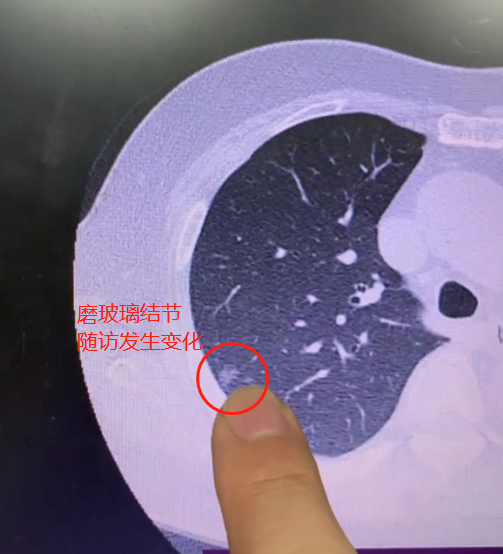

出门诊碰到一位女性患者,她右肺有个6mm大小的磨玻璃结节,一直在定期复查。

直到最近一次检查,发现最新与最早的CT对比,大小和密度都发生了变化,长到7mm左右,我就建议做手术了。

虽然这个结节比较小,但对比后发现形态更饱满,也变大了,密度增加了,就说明病灶的癌细胞已经开始生长,就没必要再拖了。

肺结节的处理,不是说非要等到8mm甚至1cm再手术,只要有变化,就需要手术切除。